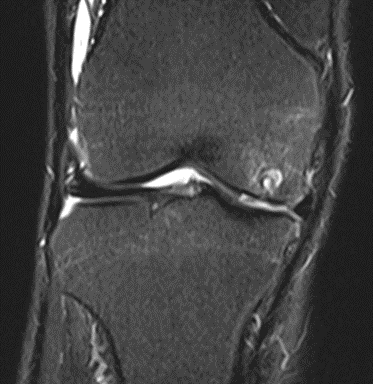

MRI scans illustrating the improvements regarding Group 2 are presented below, showing pre-treatment images with evident cartilage defects, pronounced bone marrow edema, and synovial inflammation, followed by post-treatment scans demonstrating improved joint structure, reduced edema, and decreased inflammation (Figures 12-29).

MRIs of Group 2

Figure 14: Male, 78 years, pre-intervention MRI.

Figure 15: Male of figure 14, two-month follow-up MRI: MSC plus ChondroFiller® liquid.